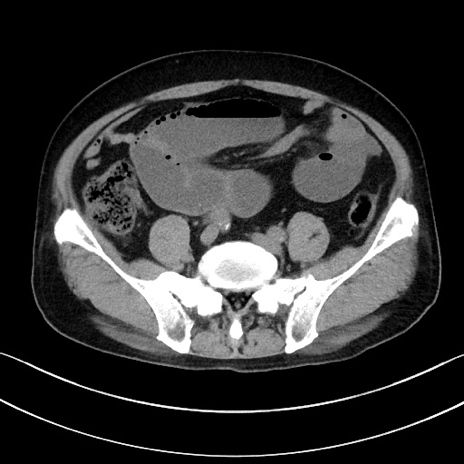

症例15(横断像)

【症例】70歳代男性

【主訴】腹痛

【現病歴】今朝から腹痛あり。全体的に痛い。特に左上の方。排ガスが今日はない。冷や汗が出る。

【既往歴】直腸癌術後

【身体所見】左側腹部〜上腹部に圧痛あり。腹膜刺激症状明らかなではない。軽度反跳痛。左下腹部に術後瘢痕あり。

【データ】WBC 7700、CRP 0.02